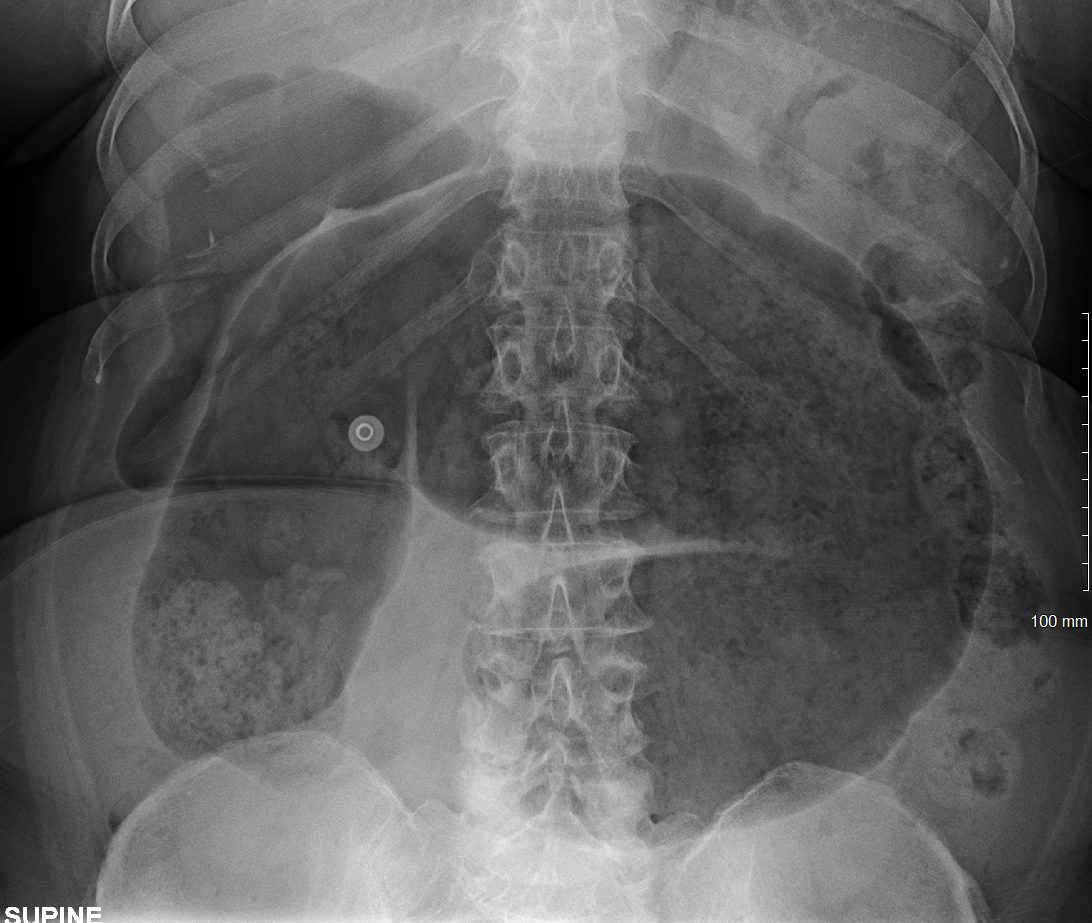

B – Looking at the film, the small bowel is not visible. There is loss of haustra markings in the transverse and descending colon. This looks like the “lead-pipe” sign which is suggestive of inflammation. There is also evidence of faecal loading in the ascending colon. The bowels are not dilated and no sign of obstruction.

In summary this AXR shows some inflammatory changes in the large bowel with loss of hautra markings and faecal loading in the ascending colon. It would be useful to see if there is previous to compare to in order to see if this is a new finding or chronic.

Lead pipe colon and faecal loading in ascending colon – found in ulcerative colitis